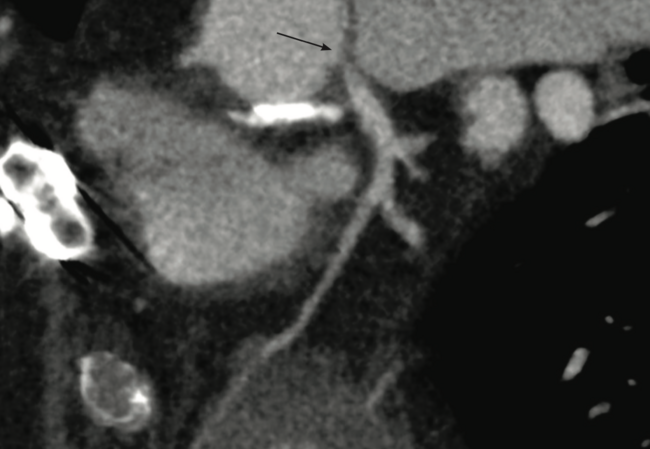

A 62-year-old gentleman presented with a past medical history significant for paroxysmal atrial fibrillation=on warfarin, type 2 diabetes mellitus, and morbid obesity. He has a complicated cardiac surgical history, with a bicuspid severe aortic valve stenosis that was managed with a surgical bioprosthetic aortic valve replacement in 2013. Later in 2021, he developed Granulicatella adiacens bioprosthetic aortic valve endocarditis, complicated by an aortic root abscess and a sizable phlegmon below the origin of the LMCA. An invasive preoperative coronary angiogram revealed normal coronary arteries. The patient underwent a redo sternotomy and an aortic valve replacement with a 25 mm On-X (CryoLife). In addition, he underwent coronary reimplantation and an ascending aorta Dacron graft repair. Six months post procedure, the patient presented with escalating angina pectoris, increased salivation, and diaphoresis. His electrocardiogram demonstrated sinus rhythm with a left bundle branch block and hemoglobin was 14 g/dL, creatinine was 1.0 mg/dL, and blood cultures were negative for any recurrence of infective endocarditis. His echocardiography revealed normal left ventricular function, and a mean gradient of 10 mm Hg across the new mechanical aortic valve with no periprosthetic regurgitation, without evidence of pericardial effusion. CTCA revealed a critical ostial LMCA stenosis (Figure 1) with no other atherosclerotic lesions in his coronary vasculature. CTCA suggested the distal LMCA measured around 6 mm, whereas the vessel distal to the lesion measured around 5 mm in diameter. The lesion length was relatively short and measured only 6 mm. Based on the CTCA, left anterior oblique 18 degrees was a good fluoroscopic view to visualize the LMCA ostium. As the patient had undergone two sternotomies, the consensus from the treating team was to manage this lesion percutaneously. In addition, the focal nature of the lesion would limit the PCI to ostium of the LMCA. Hence, the patient was pretreated with aspirin and clopidogrel.

His preprocedural international normalized ratio (INR) was 1.4. Coronary angiography was performed via the right femoral approach, which revealed a critical ostial LMCA stenosis. The right radial artery was not considered, given the bovine arch and severe tortuosity of the right subclavian artery experienced in the prior procedure. Using an Extra Backup (EBU) 3.5 6 French (Fr) launcher guide catheter (Medtronic), the lesion was wired using a workhorse wire and predilated with a 2.5 mm x 12 mm semi-compliant balloon at 12 atmospheres (atm) in order to accommodate an Eagle Eye Platinum Digital IVUS catheter (Philips). IVUS was used to assess the distal reference diameter, which was congruent with the CTCA (Video 1).